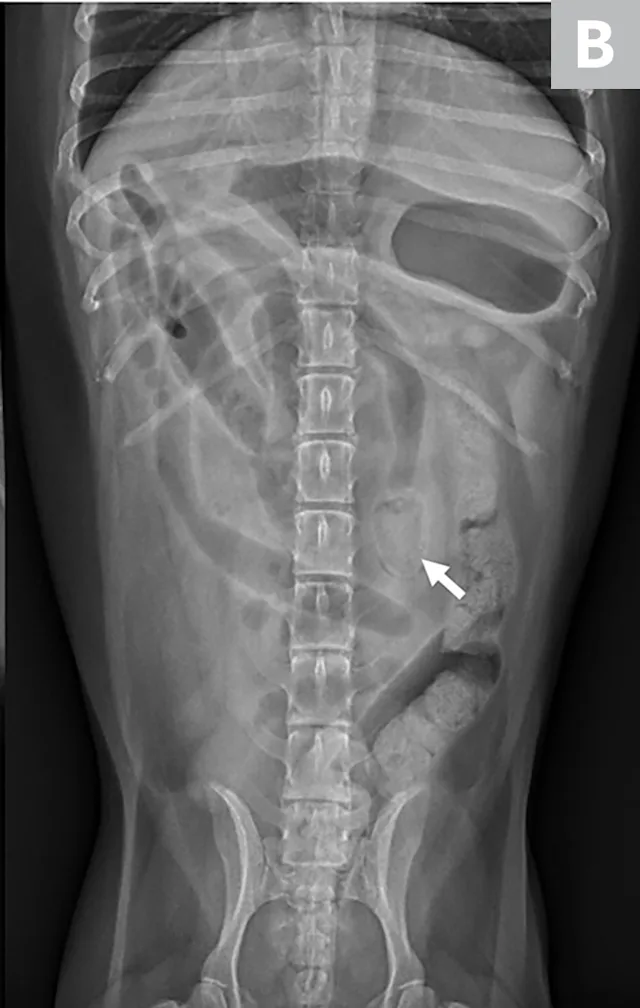

Radiographs can show segmental dilation of the bowel. In dogs, intestinal diameter measurement of >1.6 times the height of the midbody of the L5 vertebra is suggestive of intestinal dilation.1 In cats, intestinal diameter measurement of >12 mm or >2 times the height of the L2 vertebra is suggestive of intestinal dilation.1 Measurements are not definitive but can act as guidelines that can be correlated with clinical signs. As the size of the intestinal dilation increases, so do the concerns for surgical obstruction.